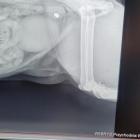

Śnieżek, jak określa „Pan Kot”, to osiedlowy pupilek, mieszkający właśnie na ulicy Białowieskiej. Z powodu kulejącej łapki został przyjęty na diagnostykę i przy okazji kastrację. W gabinecie weterynaryjnym okazał się jednak, że kot został postrzelony – badanie rentgenowskie wykazało śrut w dwóch miejscach – w udzie i łokciu. Śrut został usunięty, ale łapka nie będzie już sprawna.